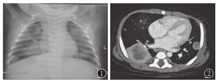

实验室检查:血常规示白细胞为(17.18~27.00)×109/L,血红蛋白、血小板正常,C反应蛋白最高135 mg/L;肝肾功能正常,降钙素原0.42 μg/L;血免疫球蛋白IgM 、IgG 、IgA、IgE正常;流式淋巴细胞亚群分类均正常;铁蛋白1 111 μg/L。血巨细胞病毒抗体阴性,1,3-β-D葡聚糖(G试验)阴性,血清半乳甘露聚糖(GM试验)2.13 μg/L(正常范围0~0.85 μg/L),γ-干扰素释放试验、血培养阴性。痰抗酸染色、真菌荧光染色、痰培养均阴性。胸片示双肺多发片状高密度影(图1)。胸CT平扫及强化示双肺多发软组织密度团块影及结节影伴边缘强化,纵隔内、右侧肺门及双侧腋窝多发淋巴结影并部分增大(图2)。胸部彩超示右侧胸腔实性包块,范围7 mm×26 mm×23 mm,考虑肺脓肿。

诊治经过:入院诊断重症肺炎、肺脓肿,予利奈唑胺联合头孢哌酮钠舒巴坦钠抗感染。入院第3天,结合患儿发热、咳嗽,肺部影像学特征性表现,血清GM试验单次>1.5 μg/L,临床诊断儿童侵袭性肺曲霉菌病[1]。予伏立康唑[负荷量9 mg/(kg·次),2次/d,1 d,改维持量8 mg/(kg·次),2次/d,静脉滴注],人免疫球蛋白(1 g/kg)。住院11 d,病情好转出院,继续口服伏立康唑[9 mg/(kg·次),2次/d]。出院后有头皮及面部的皮肤毛囊炎性丘疹。发病35 d复查G试验阳性,血清GM试验0.85 μg/L,铁蛋白降至737 μg/L。发病75 d复查胸片双肺多发片状高密度影明显吸收(图3)。服用伏立康唑随访至9月龄,未再合并感染,体质量增长至8.5 kg,生长发育适龄。